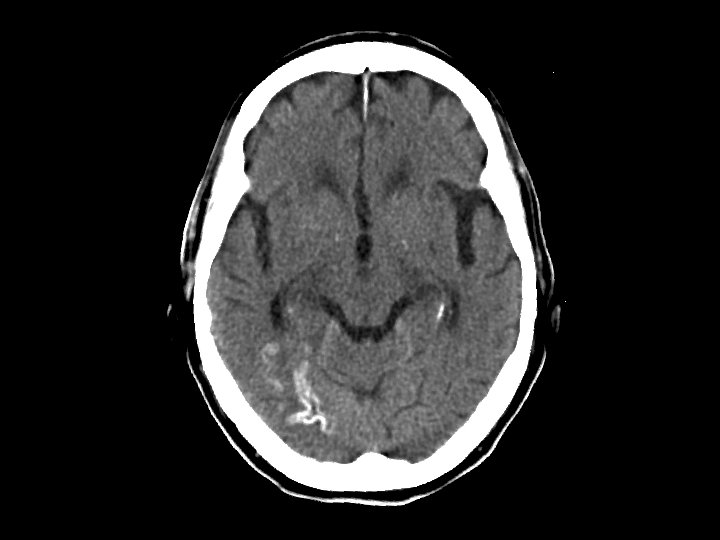

Cortical Laminar Necrosis • Findings: – Cortical calcification of the posterior right MCA territory • Due to infarction • If global, think of hypoxic injury, hypoglycemia, or encephalitis